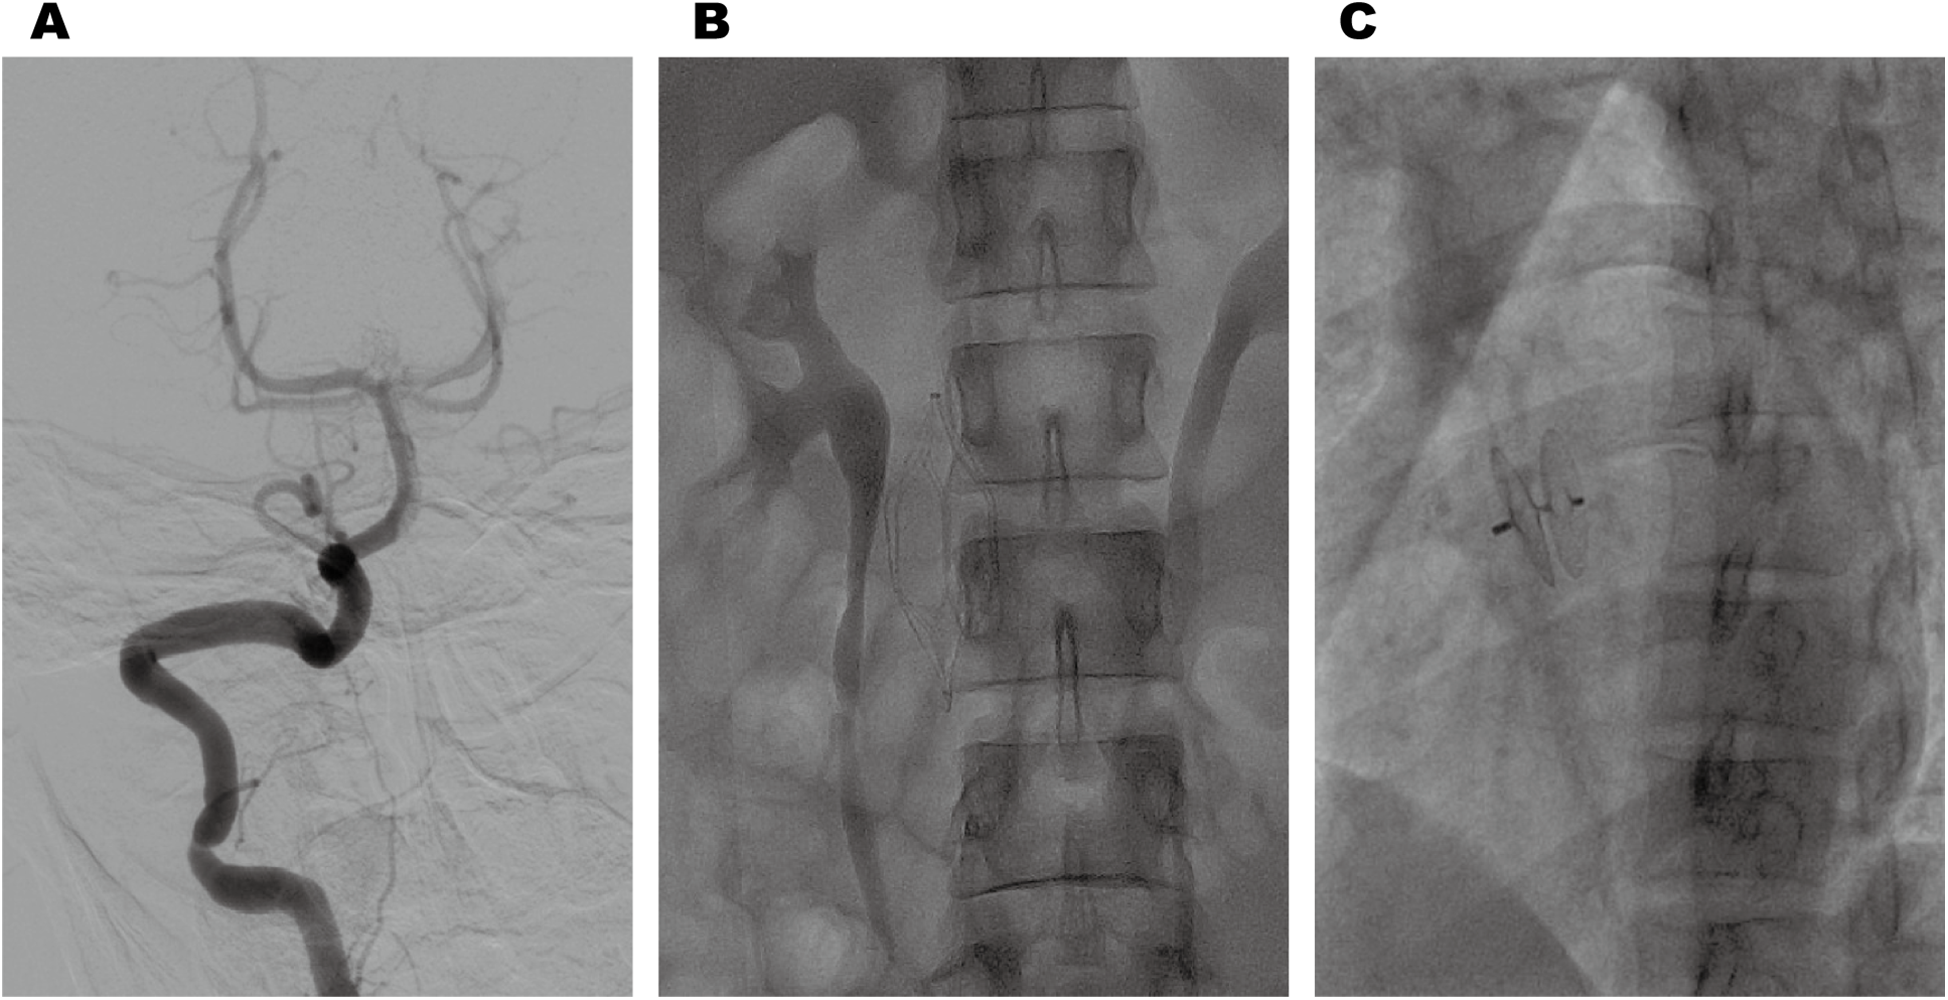

Cranial magnetic resonance imaging (MRI) revealed an acute pontine infarction (Figure 1A). Head and neck computed tomography angiography (CTA) showed basilar artery occlusion (Figure 1B) and incidentally detected left pulmonary artery embolism (Figure 1C), suggesting the possibility of multisystem embolism. Further digital subtraction angiography (DSA) of the whole brain confirmed interruption of blood flow in the distal basilar artery (Figure 2A). Pulmonary angiography revealed left pulmonary artery embolism (Figure 2B). Antegrade venography of the lower extremity deep veins showed bilateral iliac vein thrombosis (Figures 2C,D). The patient underwent emergency mechanical thrombectomy of the basilar artery and placement of an inferior vena cava filter (Figure 3B). Post-operatively, imaging evaluation showed the basilar artery was patent (Figure 3A), and the patient was transferred to the neurology department for further treatment.

Figure 3

Post-thrombectomy imaging revealed normal anterograde blood flow in the basilar artery (A). Postoperative changes following inferior vena cava filter implantation (B). Post-procedural imaging revealed appropriate positioning of the PFO closure device (C).

Based on these examinations, we confirmed that the patient with HPCD had paradoxical embolism related to PFO. After clinical stabilization, the patient underwent successful percutaneous closure of the PFO using a specific closure device (PF2525) (Figure 3C). Anticoagulation was transitioned from heparin to long-term rivaroxaban with a recommendation for lifelong therapy. At 1-year follow-up, the patient achieved complete neurological recovery (NIHSS 0, mRS 0) without recurrent thromboembolic events.